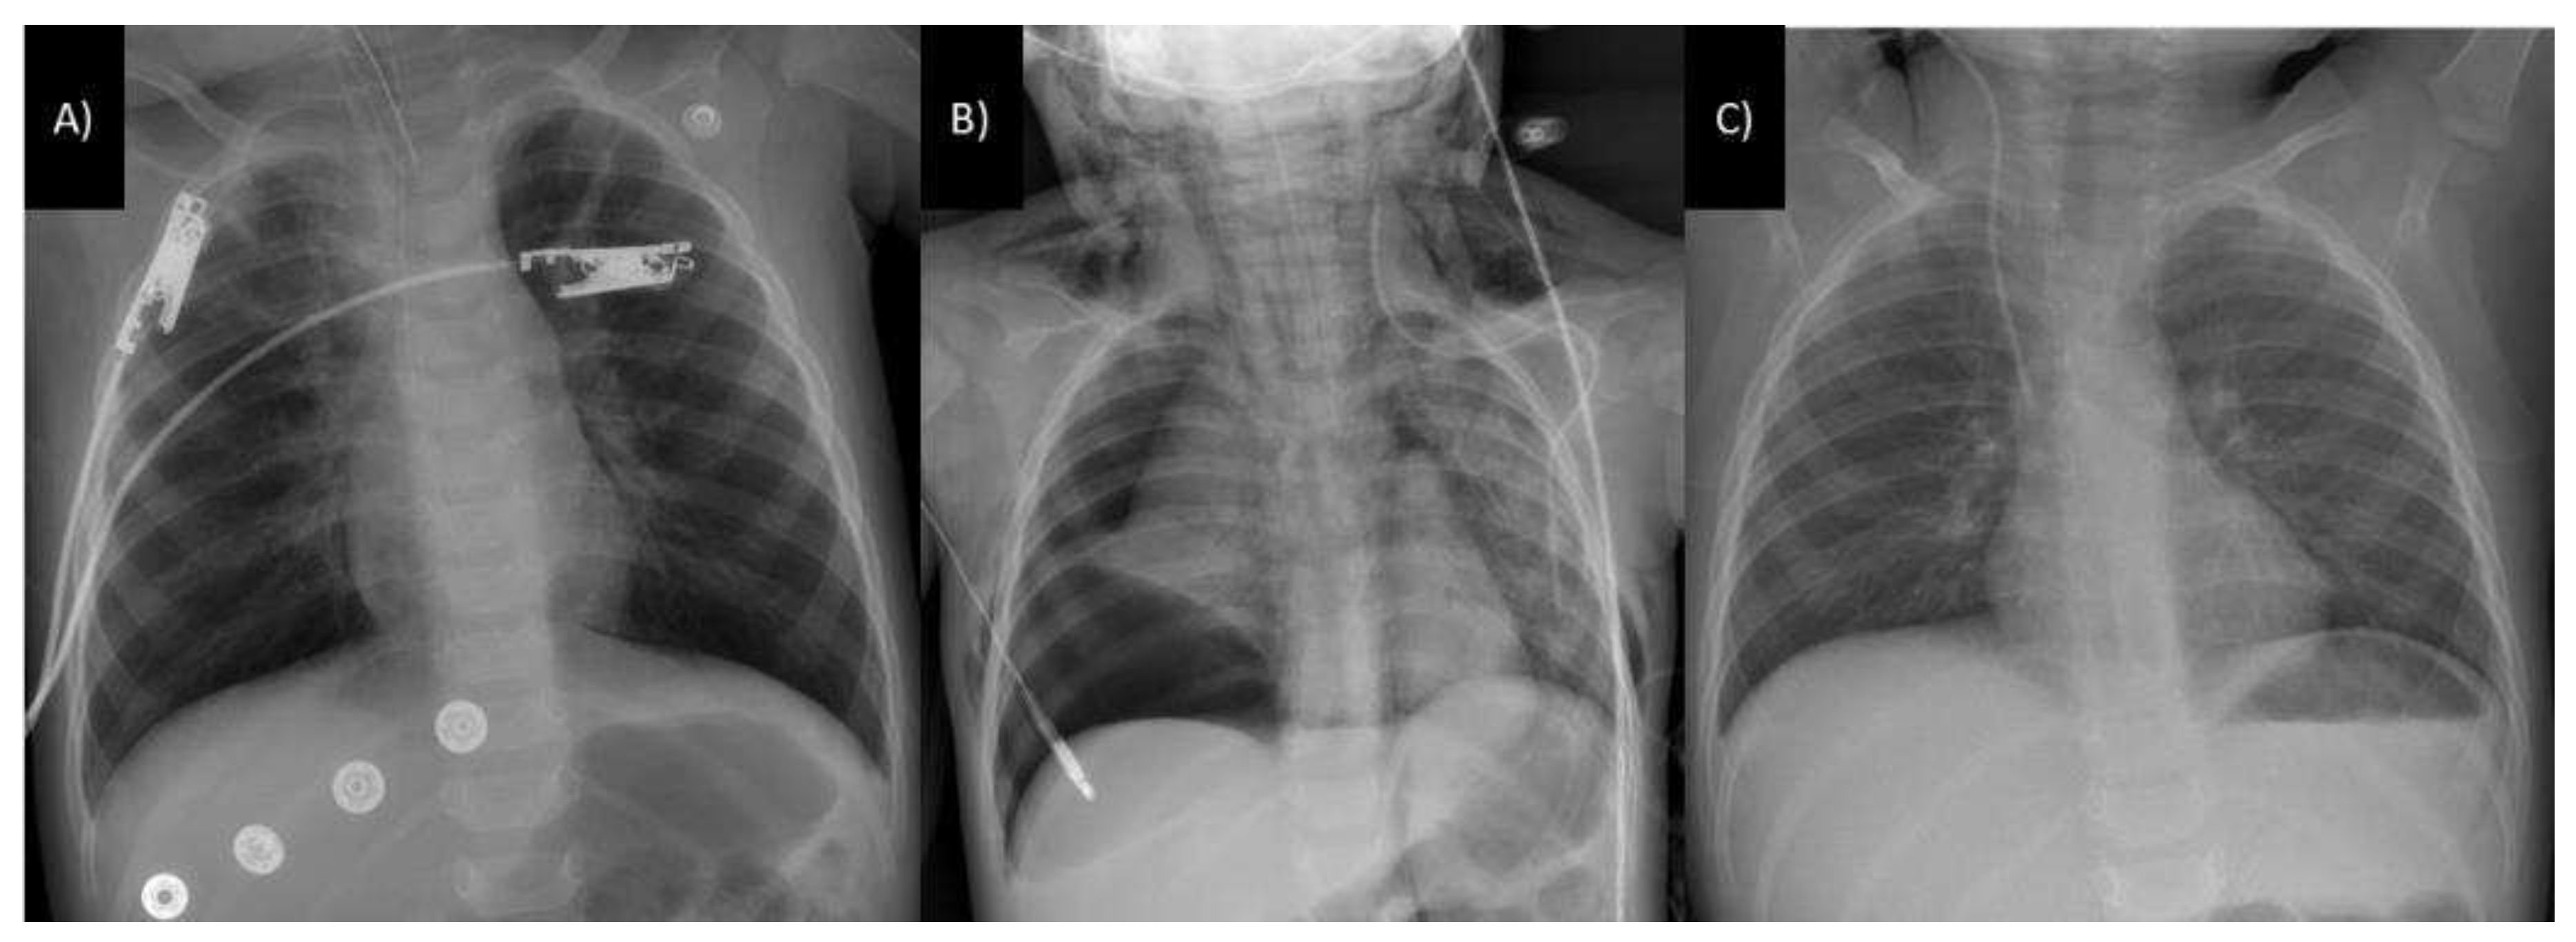

- Amit Kumar; Rajesh Chetiwal; Priyank Rastogi; Shweta Tanwar; Saurabh Gupta; Rajesh Patnaik; Maduri Vankayalapati; Sudhish Gupta; Alok Arya. Severe Esophagitis and Chemical Pneumonitis as a Consequence of Dilute Benzalkonium Chloride Ingestion: A Case Report. International Journal of Medical Students 2021. [CrossRef]